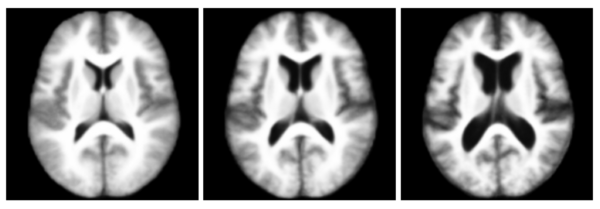

In this experiment, we used the OASIS data set [1] which consists of 416 pre-processed (skull stripped and gain-field corrected) brain MR images of subjects aged 18-96 years including individuals with early-stage Alzheimer's disease (AD). We ran iCluster on the whole data set while varying the number of templates from 2 through 6. Each run took approximately 4-8 hours on a 16 processor PC with 128GB RAM. For two- and three templates the algorithm computed unique and structurally different templates. We observed that these templates were robust: they were the same for random subsets of the data set of as little as 60 subjects. For larger number of templates, however, we observed that the computed templates were not all unique, or corresponded to single outlier subjects, or were not robust to random sub-sampling of the data set.

The following figure shows the three robust templates computed by iCluster.

Three templates of the OASIS data.

The following figure shows the difference images between the three templates shown above.

Difference between the three templates of the OASIS data